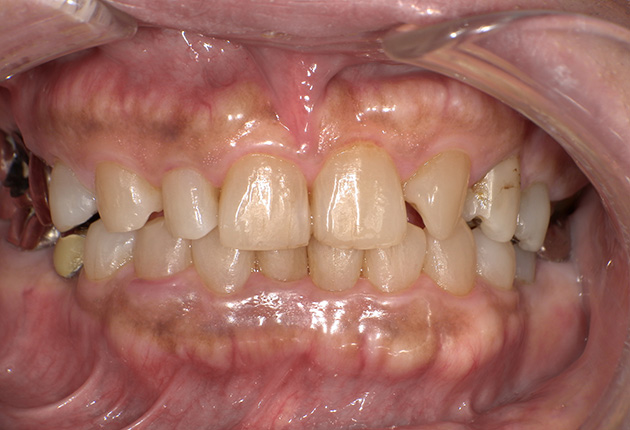

90分の治療で銀歯の状態からキレイな状態になります。噛み合わせの調整や審美面も使用しながら合わせます。

良く噛めて安心と、ご満足いただき大変嬉しく思います。笑顔も一層素敵になりました。

| 治療内容 | 欠損部インプラント 不正咬合に対し不良補綴のやり直しと合わせて咬合再構築 |